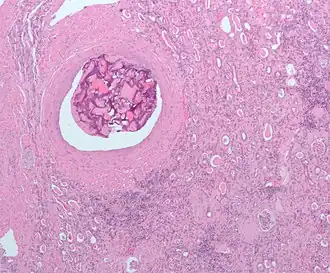

Эмболиза́ция (эмболотерапия[1]) — малоинвазивная рентгенохирургическая эндоваскулярная процедура. Состоит в избирательной окклюзии (закупорке) кровеносных сосудов специально введёнными эмболами. Выполняется интервенционным радиологом (рентгенохирургом).

Эмболизация — это малоинвазивная внутрисосудистая процедура, альтернативная традиционному хирургическому вмешательству[* 4]. Лечение направлено на предотвращение кровоснабжения определенных органов, тканей, структур организма, что помогает уменьшить размеры опухоли или блокировать аневризму.

Доступ к эмболизируемому сосуду производится с помощью катетера[7] и направителя. Иногда он затруднителен и требует больших временных затрат — всё зависит от того, какой именно орган подвергается лечению. Если точная локализация артерии или вены, снабжающей патологическое образование, неизвестна, применяется цифровая субтракционная ангиография (DSA). Полученные изображения используются радиологом для получения доступа к нужному сосуду путём выбора подходящего катетера и проволочного направителя, в зависимости от очертаний анатомических структур, окружающих этот сосуд.